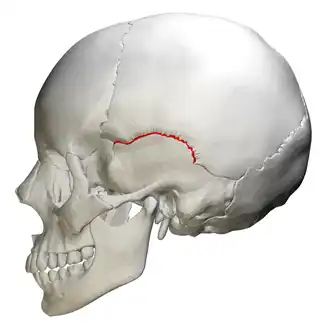

![]() Lateral view squamosal suture (red) | |

The squamosal suture, or squamous suture, arches backward from the pterion and connects the temporal squama with the lower border of the parietal bone: this suture is continuous behind with the short, nearly horizontal parietomastoid suture, which unites the mastoid process of the temporal with the region of the mastoid angle of the parietal bone. The term parietotemporal suture may refer to both of these sutures or exclusively to the parietomastoid suture and its use is, therefore, best avoided.